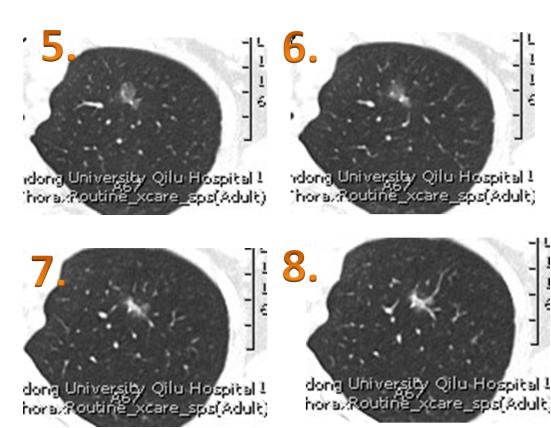

了解到您在百度贴吧给大家免费义诊,我根据报告单结节在CT片位置(im13),截取了im11-im14的片子,拜托您您评估一下。

我爱人22年1月体检首次发现磨玻璃结节(当时报告为混磨1x0.7cm);1次月后做强化CT报告为磨玻璃结节(报告大小为0.6cm,但找几位医生看后均表示与一个月前无明显改变);呼吸科医生开了抗炎药法罗培南吃了2周;3月7日在吧内向您求助,并有幸得到您的回复--“首次发现磨玻璃结节,按照指南随访3个月后复查薄层CT排除炎症后再精准诊断”。4月13日(吃了抗炎药物2月)复查了薄层CT,幸运没有降临,结节没有变化(报告显示0.8x0.6cm)。由于担心昨天发帖(您没有看到)中用的自己截的图不够清楚,怕影响您的判断;今天请影像科的同学帮忙截了图(图1-12),请您看一下。

我们今天还找另一个医院的影像科主任帮忙看了一下片子,他说结节看上去像是2个小的融合成的,重建后的图像显示结节长径到了1.5 cm,高度怀疑早期肺癌(最后一张图是重建后的图)。

左肺上叶玻璃结节,接近于纯磨玻璃,形态不规则,长经约35px (重建后测量图像),较2月10日片无变化。高度怀疑早期肺Ca,建议胸外科会诊。